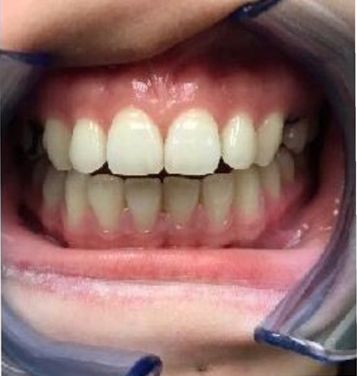

下图是我带上牙套后的样子,基本上是看不出来的,可以说是非常隐形了!

有图有真相

3.15是我安装牙套的第一天,到10.16号已经整整七个月了,不管是牙齿上的改变,和脸部的改变都还蛮大的,许久不见我的朋友都会觉得我变了个人,也很多人说我脸瘦了,其实人家不是胖啦,只是肉很多!不多说,上图

2017.03.15

2017.08.02

2017.10.17

其实还有20个牙套,但是我的凸牙已经基本上都回去了,改变巨大。下面放羞羞的真人图。

比较明显的是我的人中明显变长,嘴突有了很大改善,下巴也因此显得更长,我发现最惊喜的改变是,我的肉肉脸!!!没有了!!!

有人说我瘦了,其实我3月份的时候97斤,现在105斤,所以并不是我的体重,而是我整个脸的变化,我也是有下巴的人了!